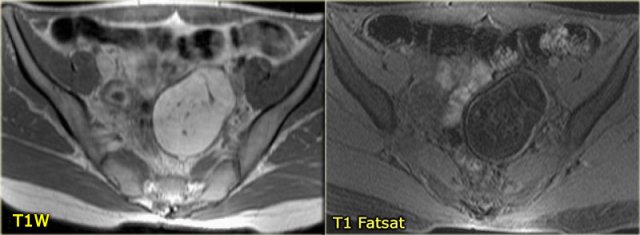

On MRI hemorrhagic cysts are bright on pre-contrast T1-FatSat, and dark on T2.

On the T1-weighted image without fatsat the complex cyst is bright, indicating either fat or blood content.

On the T1-weighted image with fatsat the lesion remains bright, ruling out a fatty lesion.

After the administration of Gd there is no enhancement, confirming that this is a hemorrhagic ovarian cyst.

On an axial T1-weighted image both lesions are bright indicating fat, blood or high protein fluid.

Fat saturation does not suppress the signal in these lesions.

In an image with overall reasonably good fat suppression this rules out a fat-containing teratoma and confirms the suggestion of hemorrhagic fluid.